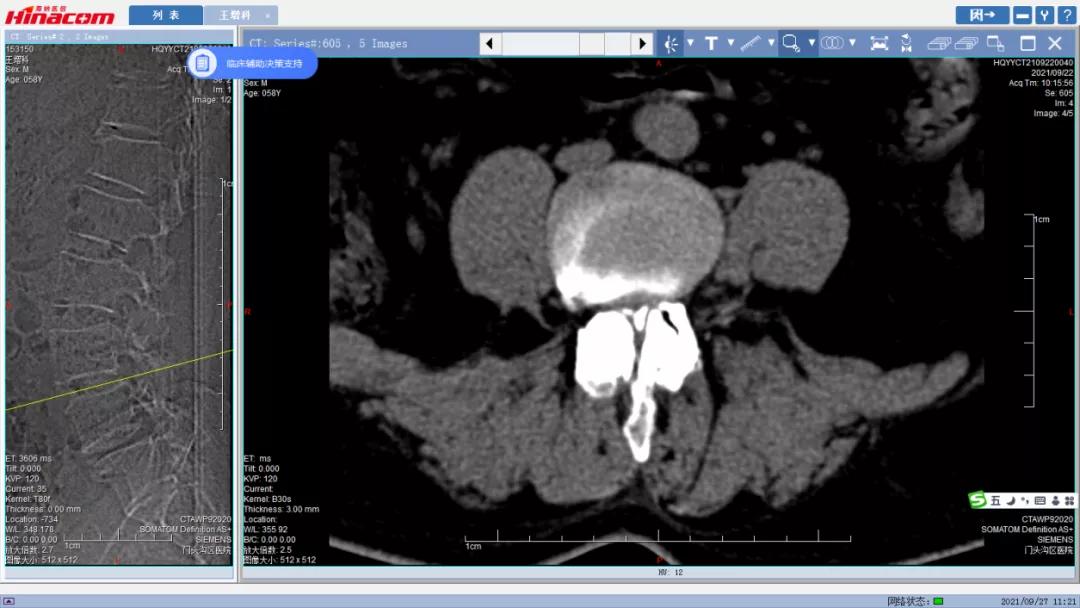

腰34椎间盘--术前CT